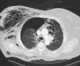

Tension pneumothorax

A pneumothorax is an abnormal collection of air in the pleural space between the lung and the chest wall. Symptoms typically include sudden onset of sharp, one-sided chest pain and shortness of breath. [Source: Wikipedia ]